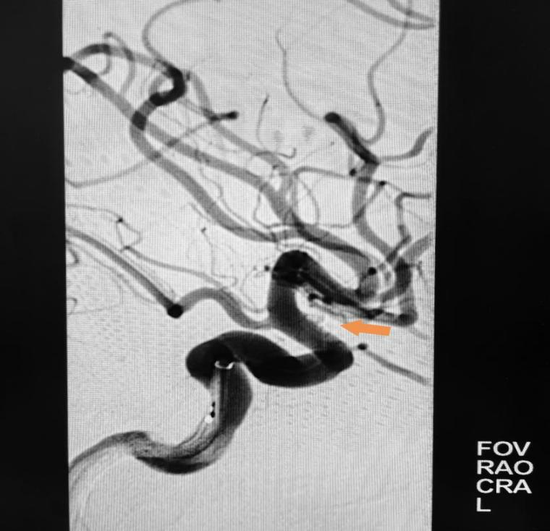

在肾病内科协助制定肾功能保护方案后,紧急完成全脑血管造影,确诊为“左侧颈内动脉眼动脉段血泡样动脉瘤”。因该类动脉瘤形态特殊,传统开颅夹闭难度大,而常规介入栓塞易复发且术中易破裂,纪文军主任医师凭借丰富的经验和对前沿技术的掌握,最终决定采用国内领先的“密网支架(血流导向装置)联合弹簧圈栓塞”术。

术前三维造影